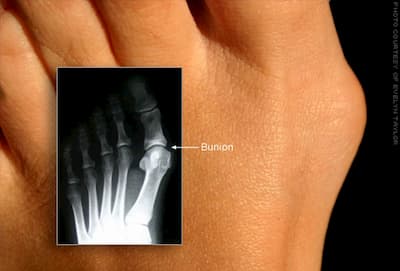

childs flat feetPeople with Down syndrome are unfortunately known to have problems with bunions, unstable ankles along with knee and hip problems.  The laxity of the ligaments is the cause of these problems since the joints are unable to stay in alignment.  Ligaments are made up of long fibers of collagen.Down syndrome is the addition of a part or whole chromosome on Chromosome 21, which is also where collagen is also formed.

Fallen archesLigaments connect bone to bone or joints where tendons connect bone to muscles.  If the ligaments are not able to support the joints, this leads to collapsing of the arches or pronation.  Pronation is the action of the arches falling and collapsing and the result is flat feet.   Approximately 95% of people with Down syndrome have flat feet.    Flat feet results in problems such as bunions, ankle instability and knee and hip subluxation.